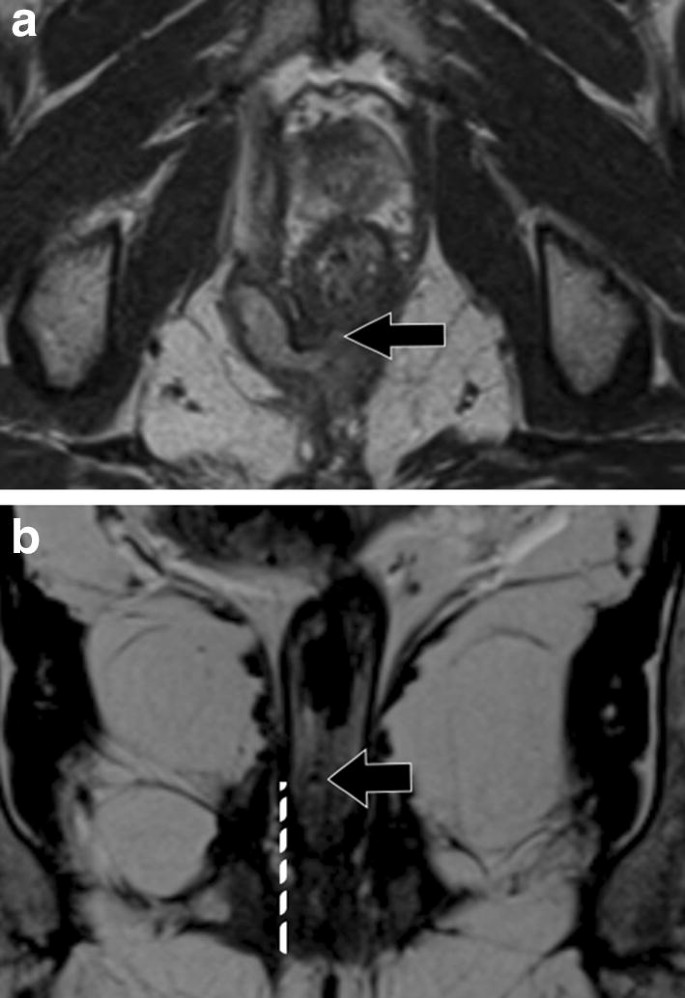

Imaging Of Acute Conditions Of The Perineum Radiographics - Fibromuscular mass located in a.

Imaging Of Acute Conditions Of The Perineum Radiographics - Muscles of the pelvic floor can be imaged with mri and pelvic floor movements can be assessed with.

Mri Anatomy Of The Anorectal Region Radiology Key - The perineal body is a midline structure formed by dense connective tissue.

Structured Reporting Of Mri For Perianal Fistula Springerlink - Fibromuscular mass located in a.